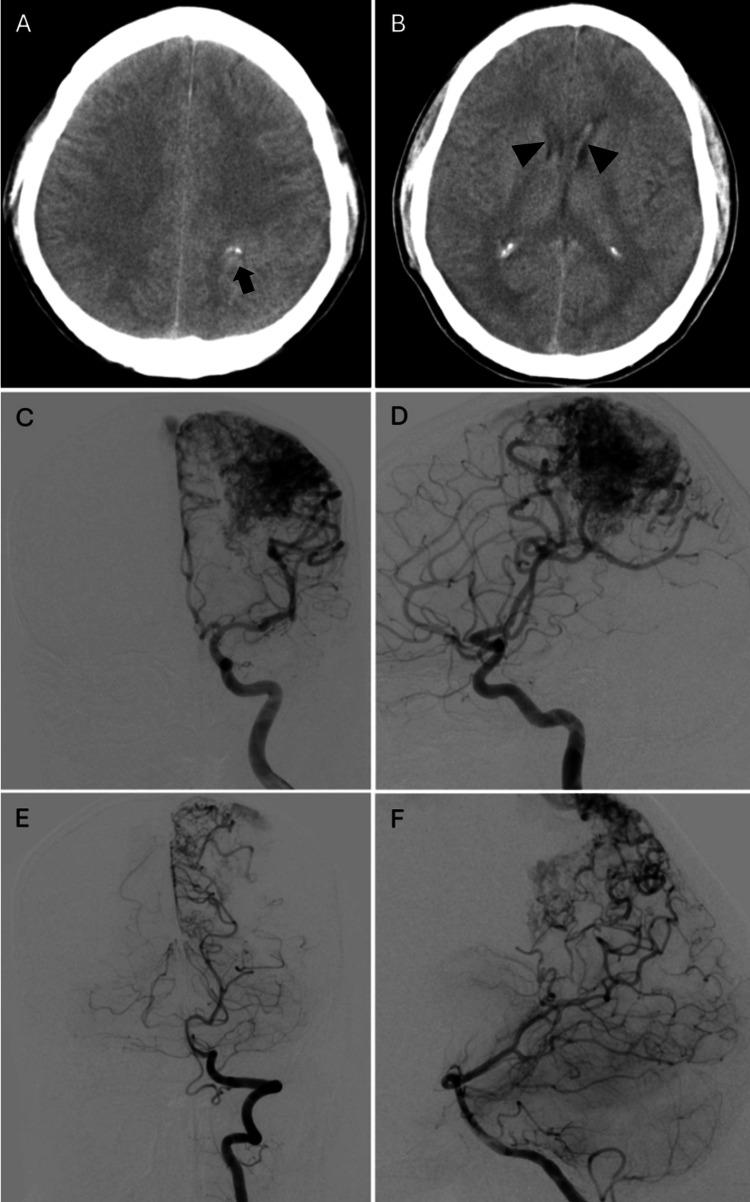

Chronic encapsulated expanding hematoma (CEEH) is a rare, delayed complication of stereotactic radiosurgery (SRS) for brain arteriovenous malformations (AVMs), often masquerading as radiation necrosis or tumor recurrence. We report the case of a 61-year-old man who developed progressive right hemiparesis and extensive steroid-resistant vasogenic edema 15 years after embolization and multisession SRS for a ruptured left parietal AVM, which had been previously confirmed as completely obliterated. Initial imaging showed a small enhancing lesion with surrounding edema, suspected to be radiation necrosis. Over the next two years, the lesion expanded with persistent edema despite corticosteroids and decompressive craniectomy. Follow-up MRI revealed classic hemorrhagic features, including a peripheral hypointense rim on T2*-GRE and SWI sequences, raising suspicion for CEEH. Surgical resection confirmed the diagnosis histopathologically and was followed by rapid clinical and radiological improvement. This case underscores the importance of considering CEEH in patients presenting with delayed symptoms and steroid-resistant edema after SRS, even when the lesion appears small. Early surgical recognition and intervention can be both diagnostic and therapeutic, preventing further morbidity.

慢性包裹性扩张性血肿(CEEH)是脑动静脉畸形(AVM)立体定向放射外科治疗(SRS)罕见的延迟并发症,常表现为放射性坏死或肿瘤复发。我们报告一例61岁男性病例,该患者在因左侧顶叶破裂性AVM行栓塞及多疗程SRS治疗15年后,出现进行性右侧偏瘫和广泛的类固醇抵抗性血管源性水肿,此前已证实该AVM完全闭塞。初始影像学检查显示一个小的强化病灶伴周围水肿,怀疑为放射性坏死。在接下来的两年里,尽管使用了皮质类固醇和去骨瓣减压术,病灶仍持续水肿并扩大。随访MRI显示出典型的出血特征,包括T2 * -GRE和SWI序列上的外周低信号环,这增加了对CEEH的怀疑。手术切除经组织病理学证实了诊断,随后临床和影像学迅速改善。该病例强调了在SRS后出现延迟症状和类固醇抵抗性水肿的患者中考虑CEEH的重要性,即使病灶看起来较小。早期手术识别和干预兼具诊断和治疗作用,可预防进一步的发病。